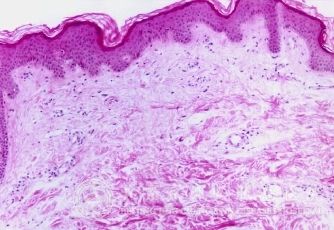

婴儿湿疹与饮食关系很大吗?很多患儿父母会问这个问题,婴儿湿疹给人们的生活工作带来了严重的影响。并且婴儿湿疹比较顽固,让人们非常烦恼,不仅给儿童的身体造成了一定的影响,而且还伴有各种不良症状,为了避免加重疾病,同时加强对皮肤病知识的了解,北京京城皮肤医院就给大家讲解, 婴儿湿疹与饮食关系。

婴儿湿疹与饮食关系很大吗?北京京城皮肤医院指出:婴儿湿疹的发生,与饮食的关系很大。研究显示:纯母乳喂养的婴儿,出现过敏(湿疹)相对较少,而喂普通婴儿奶粉的宝宝,过敏(湿疹)的发生率较高,这是因为普通婴儿奶粉中含有大分子的异体牛奶蛋白,有些宝宝不能耐受这样的蛋白质,所以出现了过敏(湿疹或食物过敏),这些宝宝将来出现其他过敏性疾病的风险会相对较高。